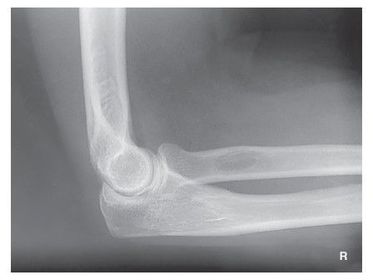

| Lateral Elbow | The elbow is elevated above the level of the shoulder radial head anterior to coronoid - should be superimposed capitulum too proximal to trochlea radial tuberosity seen - hand is pronated |

| Lateral Elbow | Elbow is depressed below the level of the shoulder radial head superimposed by coronoid capitulum too distal to medial trochlea |

| Lateral Elbow | the distal wrist is elevated hand is pronated because you can see the radial tuberosity - should not see that |

| Lateral Elbow Evaluation Criteria | ANATOMY: distal humerus, proximal forearm, entire elbow joint CRITERIA: humeral epicondyles are superimposed radial tuberosity is invisible (if visible the hand is pronated) half of the radial head superimposed by coronoid process Elbow is flexed 90 degrees to see/not see fad pads 3 concentric arcs visible POSITIONING: CR perpendicular @ lateral epicondyle |